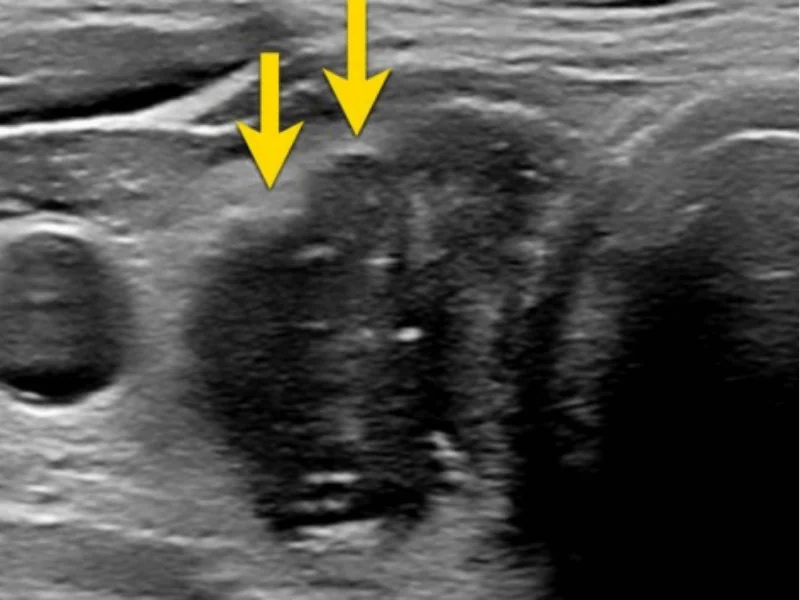

Característica #3: Ecogenicidade ⭐ (MAIS IMPORTANTE)

É a "cor" do nódulo no ultrassom.

Hipoecoico (mais escuro que tireoide):

- 🔴 MAIS SUSPEITO

- Aparece cinza/escuro

- Maioria dos cânceres é hipoecoico

- MAS: maioria dos hipoecoicos ainda é benigno!

Marcadamente hipoecoico (muito escuro):

- 🔴🔴 MUITO SUSPEITO

- Mais escuro que músculos do pescoço

- Risco câncer: 30-50%

- Indicação forte de PAAF